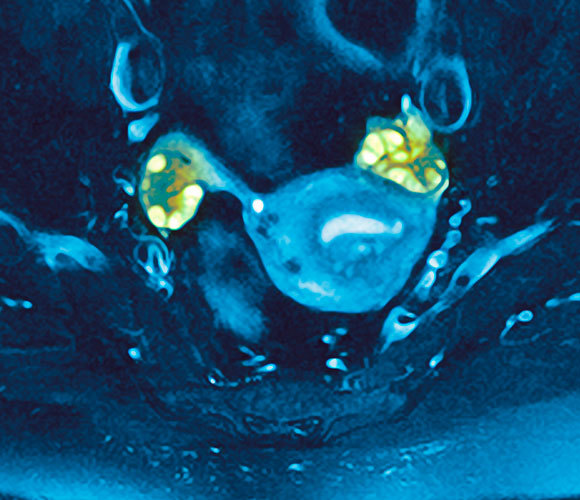

آليّة عمل معقّدة للمرض. صورة تظهِر تكيّس المبيضَين (بالأخضر) بواسطة ال MRI | المصدر: GUSTOIMAGES / SCIENCE PHOTO LIBRARY